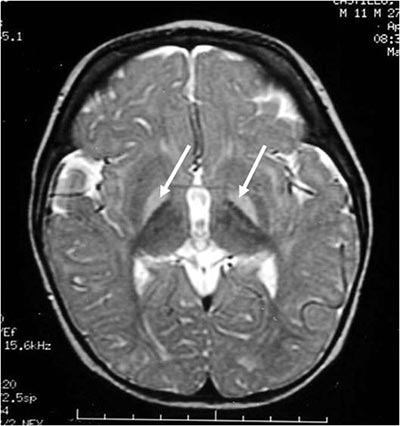

Kernicterus occurs when prolonged high bilirubin levels allow bilirubin to cross the blood-brain barrier. Bilirubin is then deposited into the brain, causing severe brain damage and cerebral palsy.

But uncontrolled hyperbilirubinemia can cause bilirubin to cross the blood-brain barrier. When bilirubin is deposited into the brain, severe, irreversible brain damage can occur. This is called kernicterus.